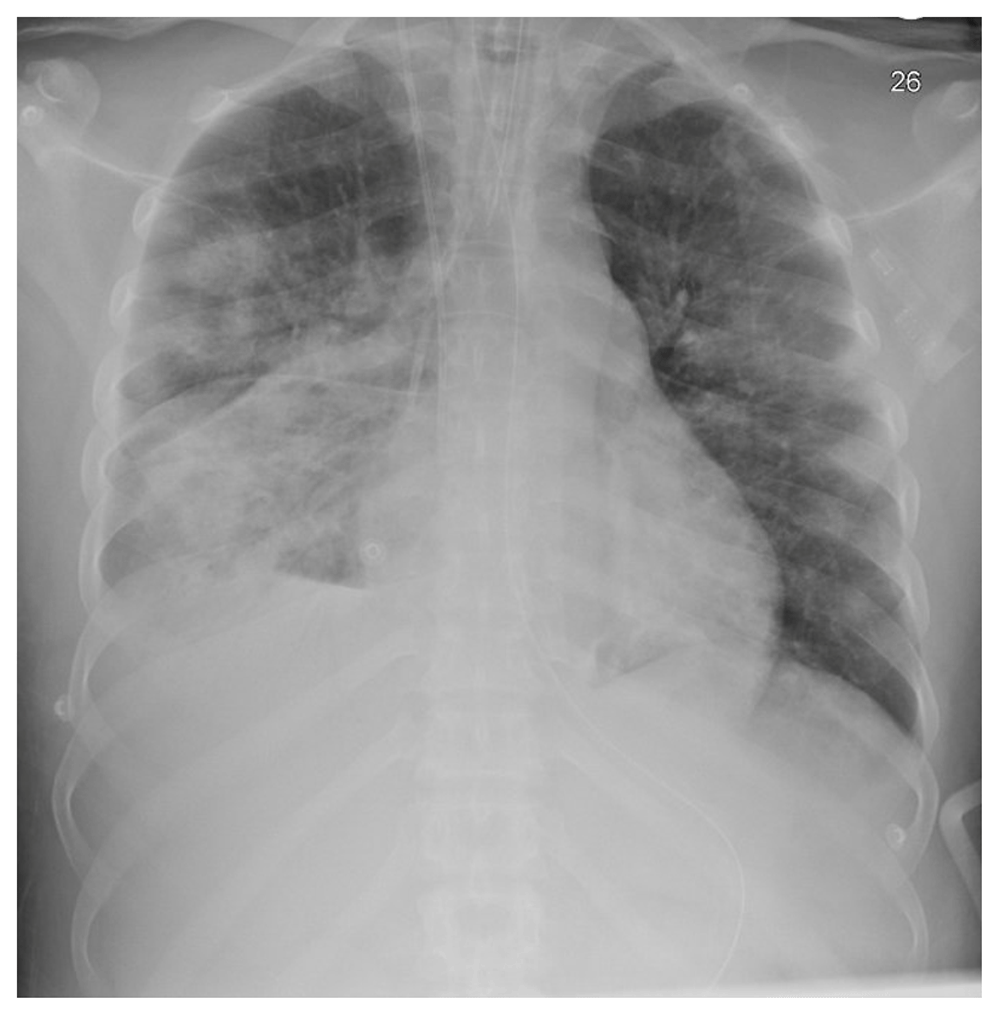

The patient was started on continuous renal replacement therapy (CRRT); his clinical status deteriorated with increased ventilation requirement of FiO2 50% to 80%, PEEP 8 to 16 cm H2O on day 4. A chest X-ray showed multiple bilateral ill-defined patchy opacities in the right lower lung zone (Figure 1). A computed tomography (CT) scan for his chest was done and showed multiple bilateral patchy ground-glass opacities (Figure 2, Figure 3). Bilateral lower lobe consolidations with air bronchogram showed greater involvement of the right lower lobe, while an unenhanced CT of the brain demonstrated hyperdense foci seen in the left inferior frontal, right parietal lobes with surrounding edema, and right central sulcus compatible with intra-parenchymal hemorrhage and subarachnoid hemorrhage, respectively. A follow-up MRI of the brain was obtained, showing an increased gyral pattern of T1 and FLAIR sequence, as observed in the bilateral occipital, bilateral frontal, and right parietal lobes, likely related to laminar necrosis from the anoxic- ischemic event. Gradient recalled echo (GRE) sequence showed scattered areas of blooming artifacts that are likely to be related to recent extensive hemorrhage. The brain findings were suggestive of hemorrhage and hypoxic injuries of vascular causes of previous cardiac arrest events.

The radiograph shows multiple bilateral ill-defined patchy opacities more in the right lower lung zone.